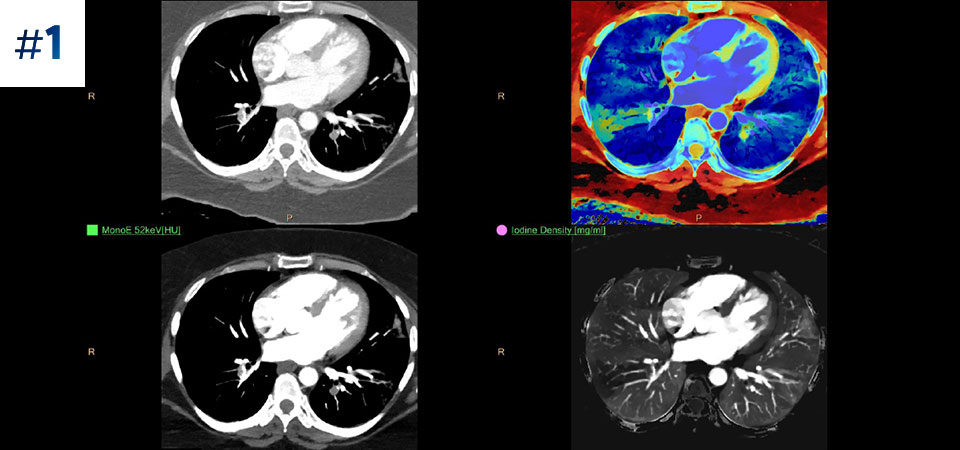

Conservez vos repères Une seule acquisition pour des données conventionnelles et spectrales rapides et à faible dose pour chaque patient, à chaque fois.

Toujours disponible 100% spectral, 100% du temps pour des résultats toujours disponibles même de façon rétrospective.

Notre scanner à détection spectrale Philips nous permet d'acquérir des données conventionnelles et spectrales en une seule acquisition, sans changement dans notre flux de travail actuel.